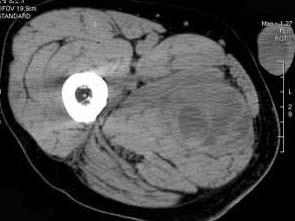

问题 男,30岁,主诉右大腿肿块年余,逐渐增大,局部胀痛及压痛,请根据图像表现,选出最佳选项 ( )

选项 A、横纹肌肉瘤 B、神经纤维瘤 C、血管瘤 D、脂肪瘤 E、脓肿

答案 A